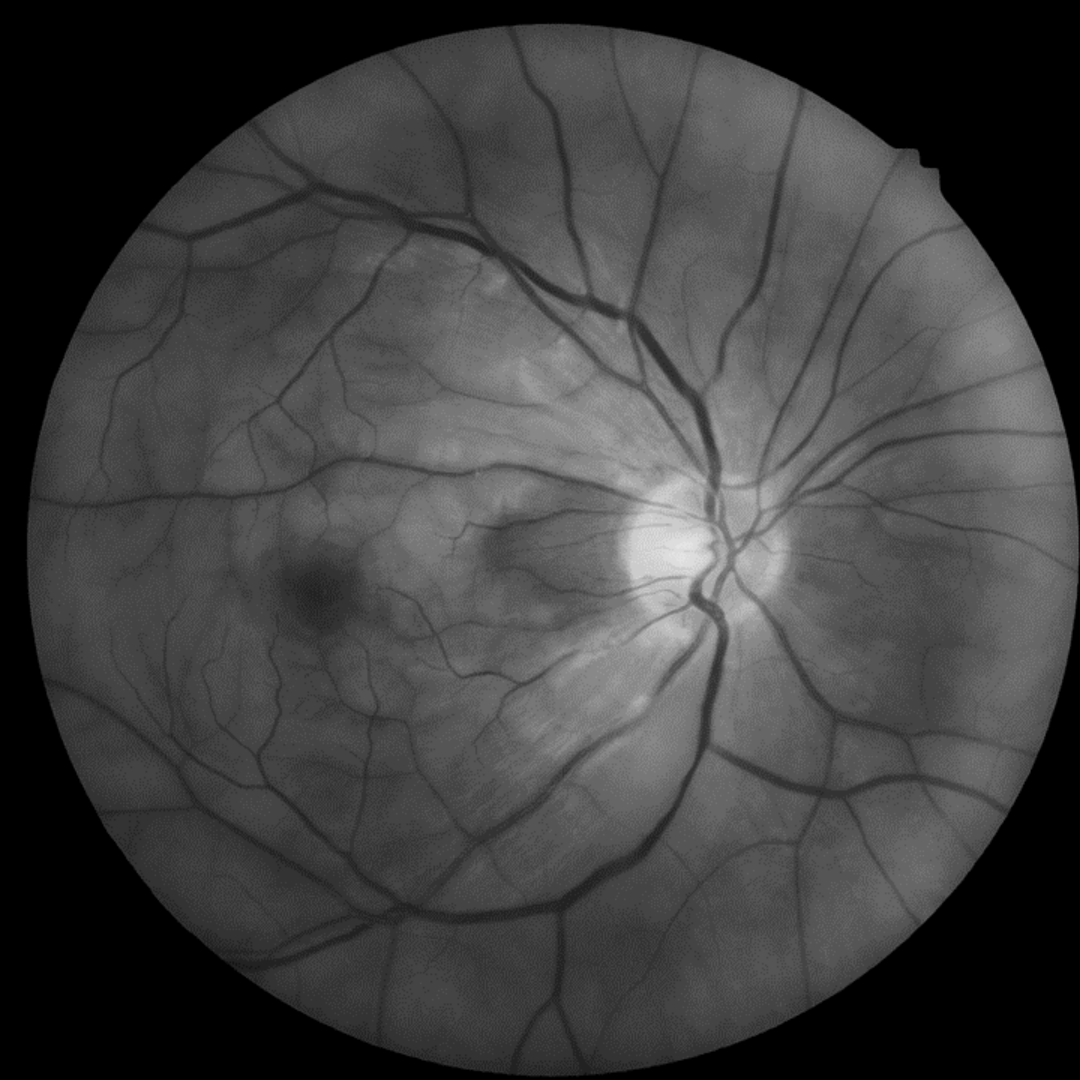

A 66-year-old Caucasian male with a sudden loss of vision in the right eye. He was diagnosed with a central retinal artery occlusion by an ophthalmologist. Images from a one-month follow-up appointment have also been included.

A CRAO means that there is no oxygenated blood reaching the retina, so it quickly becomes ischaemic and swelling of the retinal nerve fibre layer ensues, causing most of the retina to appear white and opaque. The exception to this is the fovea which retains its normal red colour. This is due to the fact that the central macula is characterised by the foveal avascular zone. In this area, the inner retina is physiologically absent so the swelling and whitening of the RNFL does not affect this zone and the practitioner can visualise the normal red colour of the choroidal circulation (supplied by the posterior ciliary arteries rather than the central retinal artery).

Up to 50% of people have an anomalous additional branch to their short posterior ciliary artery supplying the papillomacular bundle, known as a cilioretinal artery. If a cilioretinal artery is present, the area between the disc and macula (papillomacular area) can remain well perfused, and the vision may be relatively spared.